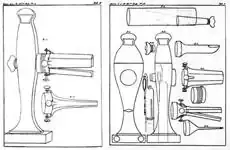

- В 1806 году Филипп Боццини изобрёл первый эндоскоп, который он предполагал использовать для исследования мочевыделительных органов и прямой кишки, названный им «Lichtleiter» («проводник света»)[10].

- Адольф Куссмауль в 1868 году ввёл в практику гастроскопию с помощью металлической трубки с гибким обтуратором, а 1869-м — предложил аспирацию желудочного содержимого с помощью желудочных зондов с целью исследования состояния желудка[12].

- В 1871 году Карл Штёрк продемонстрировал эндоскоп из двух металлических трубок, сделанный на основе высказанной в 1870 году Луисом Валенбургом идеи[13].

Гастроинтестинальная эндоскопия

Эндоскопические исследования выполняются с помощью специальных аппаратов-эндоскопов, вводимых пациенту через естественные отверстия — рот или задний проход и передающих изображение в исследуемом органе или на окуляр эндоскопа или на монитор. В современной практике используются два типа гибких эндоскопов: волоконно-оптические фиброэндоскопы и видеоэндоскопы, оцифровывающие видимую в объектив картинку и передающие её в таком виде на монитор или окуляр. Эзофаго-, гастро-, дуодено- и/или еюноскопия показаны при подозрении на воспаление или язву, а также другие заболевания пищевода, желудка, тонкой кишки, фатерова сосочка. Колоноскопия — эндоскопическое исследование толстой кишки, показана при наличии клинических признаков, указывающих на поражение толстой кишки, наблюдении за пациентом в процессе лечения, при осмотрах, направленных на выявление на ранней стадии онкологических и других заболеваний[22].

- Эндоскопические исследования пищевода, желудка и кишечника

Гибкий волоконно-оптический фиброэндоскоп